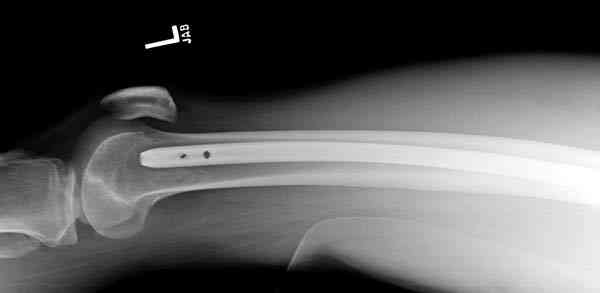

Несмотря на высокоэнергетический характер ранения, пуля не попала непосредственно в кость, а прошла рядом. Таким образом, для бедренной кости это ранение нельзя назватьв полном смысле этого слова высокоэнергетическим. К сожалению, не видно выходное отверстие. В любом случае, при таком переломе интрамедуллярный остеосинтез вполне показан. Кроме того, если пациент попал к Вам в первые часы после ранения, рана не должна рассматриваться как инфицированная. В качестве примера возможности даже более травматичной операции при таком характере перелома привожу следующий случай.

Пациент оперирован на 5-е сутки (переведен из другого лечебного учреждения)после сквозного пулевого ранения плеча и грудной клетки (непроникающее ранение той же пулей). Выполнен минимально инвазивный остеосинтез блокируемой метадиафизарной пластиной, повторная хирургическая обработка ран плеча. Заживление всех ран первичное, сращение наступило в обычные сроки.